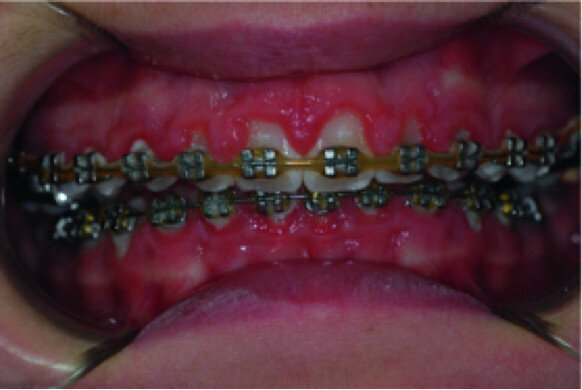

Surgical laser-assisted treatment via laser gingivectomy.

A 14-year-old female patient was referred to our department by the orthodontics unit because, at the end of fixed orthodontic treatment, she had developed gingival enlargement in the upper arch (Fig. 1), probably related to the fast closure of the spaces associated with very poor oral hygiene due to bleeding during toothbrushing. Just after the removal of the appliance, a topical anaesthetic (EMLA, AstraZeneca) was applied to the gingivae (Fig. 2) and a gingivectomy was performed using a diode laser (XD-2, Fotona) according to the technique of removal of the inter dental papillae (Fig. 3). The parameters used were as follows: a wavelength of 808 nm, 3 W in continuous wave, a 320 μm fibre in contact mode. The intervention had a duration of 375 seconds, and the patient did not feel any pain (Fig. 4). After the intervention, the patient did not take any kind of pain medication, and the healing process was completed in five days (Fig. 5).